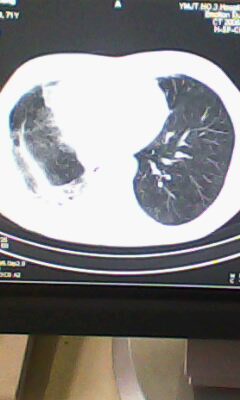

标题: CT25675:男 71 肺癌部分切除术后 3年 [打印本页]

标题: CT25675:男 71 肺癌部分切除术后 3年

两肺感染性病变,右侧肺膨胀不全,左侧上叶结节影及左侧颈部淋巴结肿大建议复查。

1)两肺感染性病变。2)右侧胸膜增厚。3)冠状动脉及主动脉钙化。

右肺癌切除术后。

右肺炎症,左肺炎症。

右侧胸膜肥厚。

1.右肺符合肿瘤切除术后ct表现。

2.左肺炎症。

术后改变,双肺内纤维索条影考虑与放疗有关。